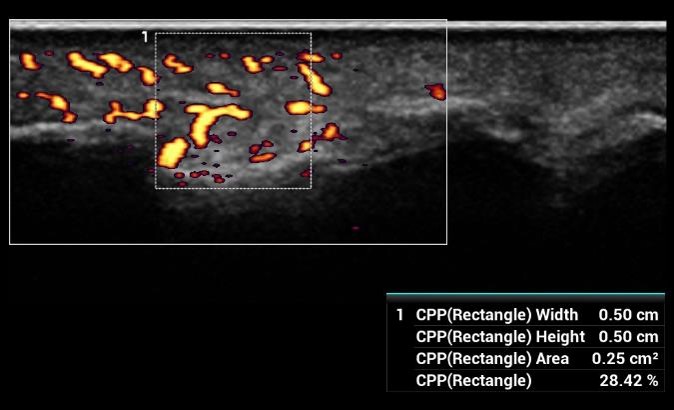

CPP - Percento farebných pixelov, výpočet percentuálneho podielu farebných pixelov v rámci definovanej oblasti záujmu

CPP: Vhodné na diagnostiku extrémne jemných prietokov (napr. reumatoidná artritída). Automatická štatistika percentuálneho podielu farebných pixelov v rámci vyšetrovanej oblasti.

CPP: Vhodné na diagnostiku extrémne jemných prietokov (napr. reumatoidná artritída). Automatická štatistika percentuálneho podielu farebných pixelov v rámci vyšetrovanej oblasti.

CPP: Vhodné na diagnostiku extrémne jemných prietokov (napr. reumatoidná artritída). Automatická štatistika percentuálneho podielu farebných pixelov v rámci vyšetrovanej oblasti.

CPP - Percento farebných pixelov, výpočet percentuálneho podielu farebných pixelov v rámci definovanej oblasti záujmu